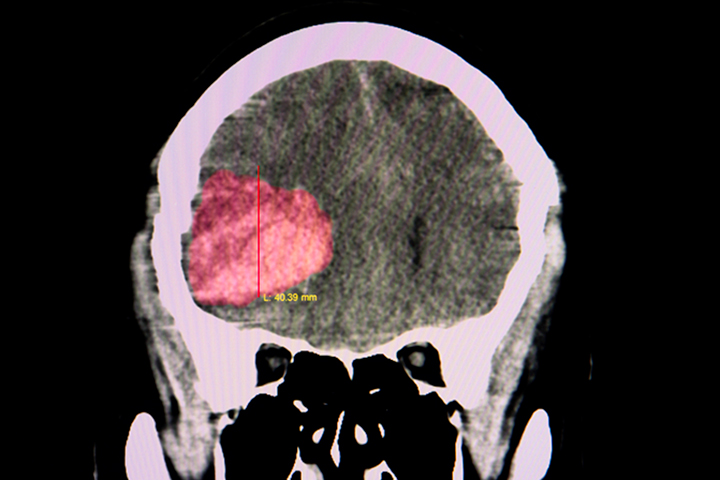

Terapia antiplaquetaria después de un accidente cerebrovascular por hemorragia intracerebral

Lancet, 22 de mayo de 2019  Estos resultados excluyen todo, excepto un aumento muy modesto en el riesgo de hemorragia intracerebral recurrente con terapia antiplaquetaria en pacientes en terapia antitrombótica para la prevención de la enfermedad vascular oclusiva cuando desarrollaron hemorragia intracerebral. El riesgo de hemorragia intracerebral recurrente es probablemente demasiado pequeño para exceder los beneficios establecidos de la terapia antiplaquetaria para la prevención secundaria.